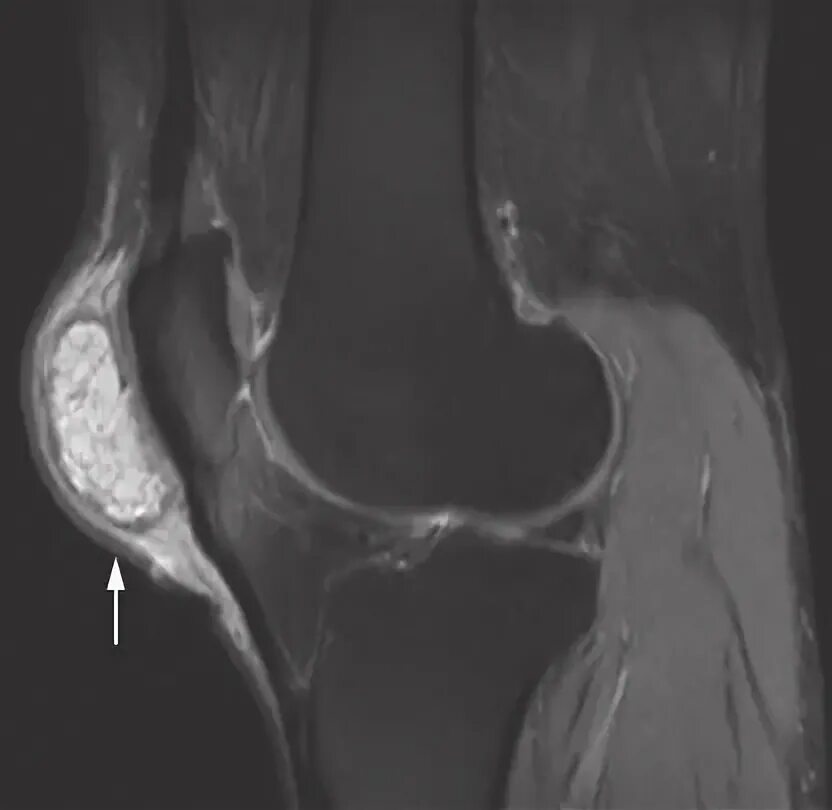

Что такое синовит коленного сустава на мрт